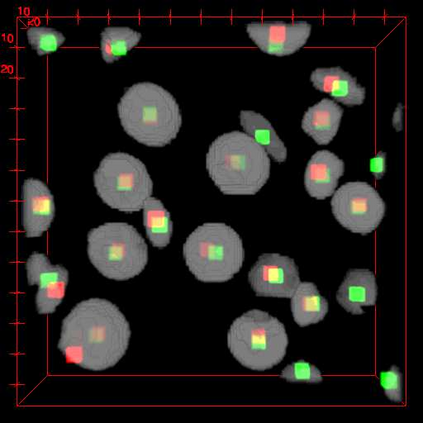

Robust and accurate nuclei centroid detection is important for the understanding of biological structures in fluorescence microscopy images. Existing automated nuclei localization methods face three main challenges: (1) Most of object detection methods work only on 2D images and are difficult to extend to 3D volumes; (2) Segmentation-based models can be used on 3D volumes but it is computational expensive for large microscopy volumes and they have difficulty distinguishing different instances of objects; (3) Hand annotated ground truth is limited for 3D microscopy volumes. To address these issues, we present a scalable approach for nuclei centroid detection of 3D microscopy volumes. We describe the RCNN-SliceNet to detect 2D nuclei centroids for each slice of the volume from different directions and 3D agglomerative hierarchical clustering (AHC) is used to estimate the 3D centroids of nuclei in a volume. The model was trained with the synthetic microscopy data generated using Spatially Constrained Cycle-Consistent Adversarial Networks (SpCycleGAN) and tested on different types of real 3D microscopy data. Extensive experimental results demonstrate that our proposed method can accurately count and detect the nuclei centroids in a 3D microscopy volume.